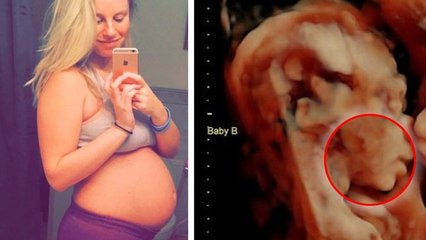

Cette jeune femme de 23 ans croyait être enceinte de jumeaux, mais quand le docteur lui montre l’échographie…